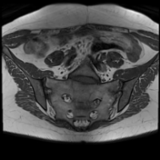

Active axial spondyloarthritis with advanced structural lesions